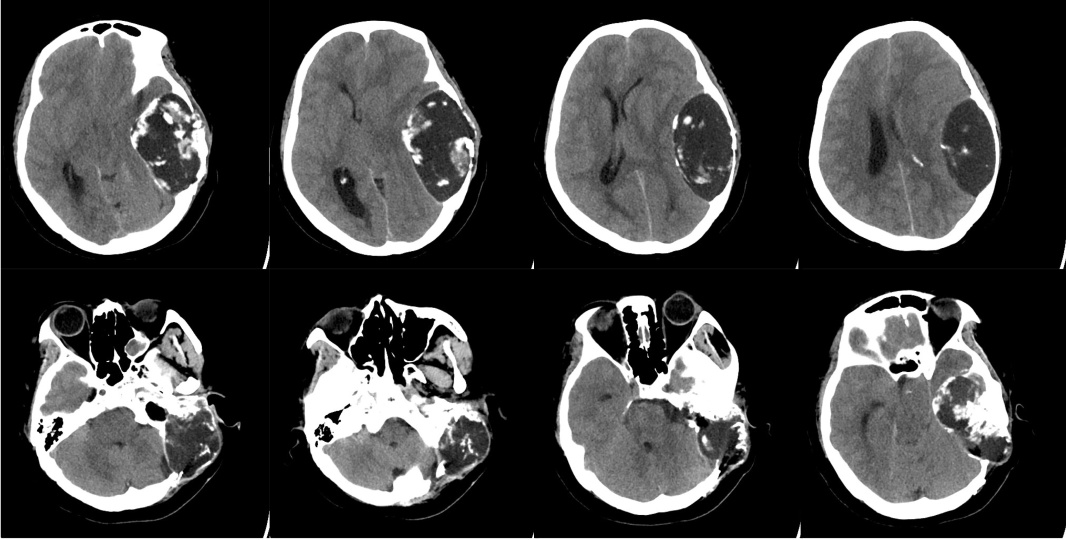

CT显示左侧中颅底软骨肉瘤

几天后,岳琪博士接到了县医院神经外科副主任医师陈朝华的电话,一位41岁的女性患者因头痛、嗜睡来到急诊,头颅CT显示左侧中后颅底巨大占位,病灶侵蚀岩骨、包绕颈内动脉,中线明显偏移,但患者家庭经济状况不佳,仅希望保守治疗。岳琪医生分析病情后,认为开颅手术是目前降低颅高压、延长生存时间的唯一手段,断然放弃实属可惜,于是向援滇医疗队汇报,大家提出申请救助金等方法解决患者后顾之忧,患者家属同意手术治疗。针对这位患者,周支瑞医生、岳琪医生和洪娟医生展开多学科协作,制定了幕上下联合入路切除肿瘤、辅以术后放疗的治疗方案。手术顺利实施,患者将于近期出院。